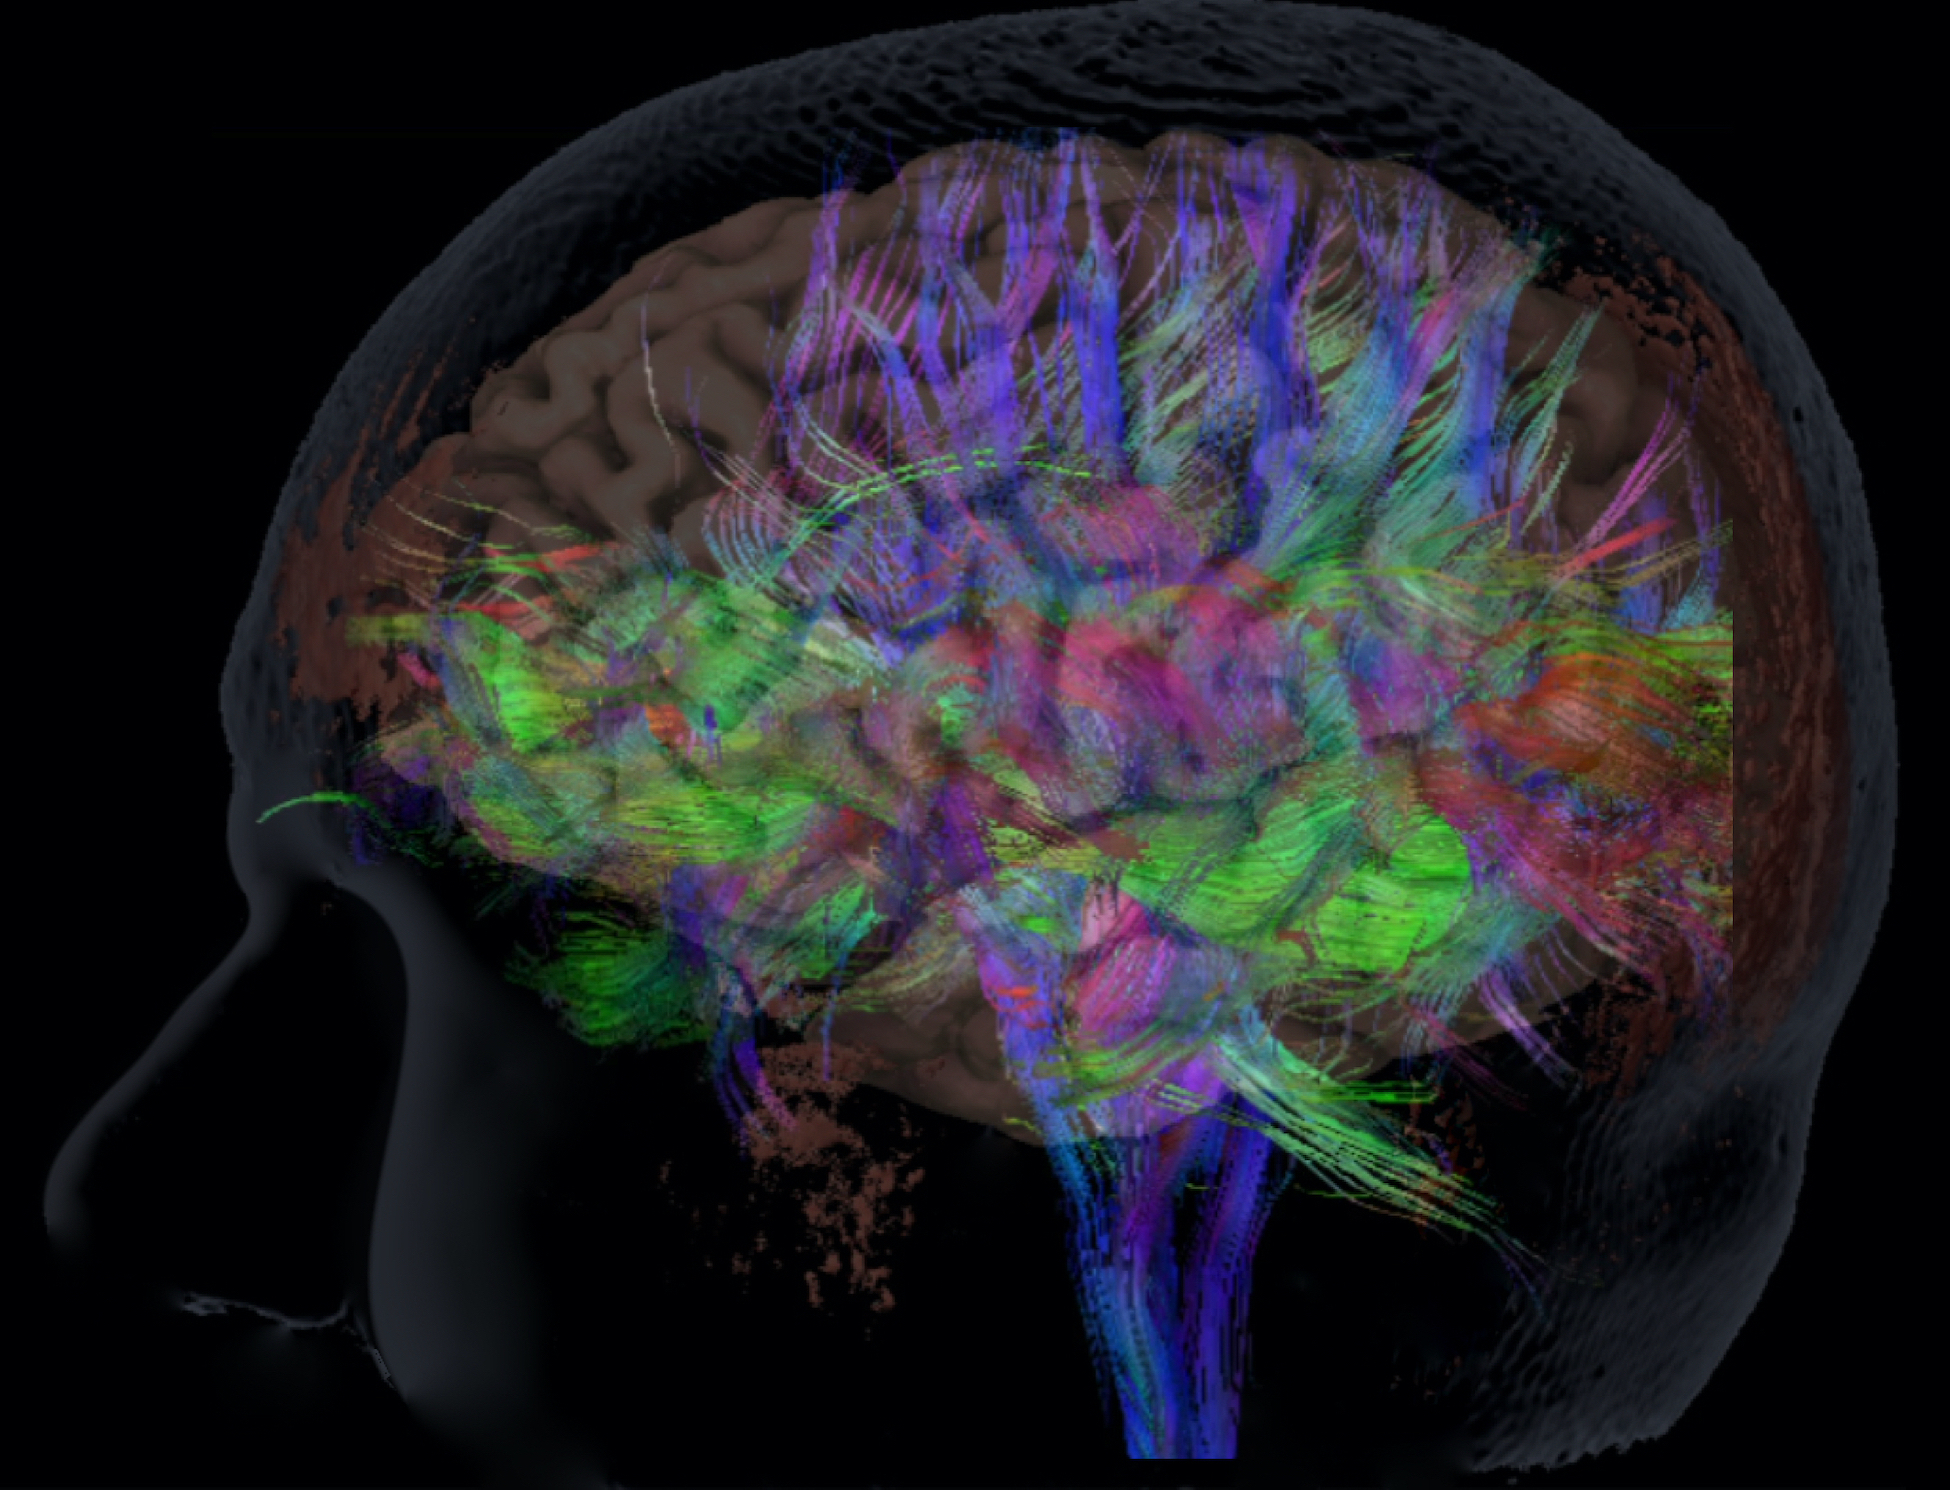

Om te beginnen, innovatie in beeldvorming. Welke technieken hebben we nu al voorhanden? U heeft al gezien dat we de functie van de hersenen in beeld kunnen brengen met functionele MRI. Ook kunnen we de vezelbanen binnen de hersenen afbeelden.

Vezelbanen in de hersenen afgebeeld met MRI.

Ook deze zijn van groot belang voor een operatie, want het doornemen van de verbinding – het doorknippen van de bekabeling als het ware – kan net zulke ernstige gevolgen hebben voor de patiënt als het beschadigen van het functionele hersengebied zelf.